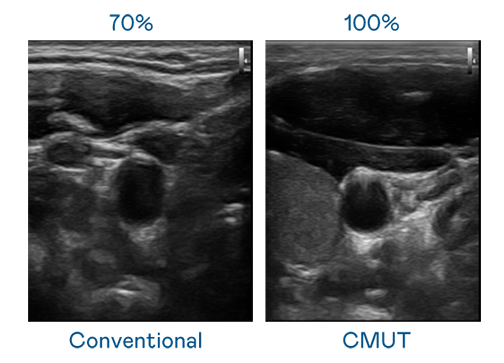

CMUT 技术是一种用电容式微机电元件来产生超音波讯号的技术。与传统 PZT 压电式技术相比,CMUT 频宽增加 30%,更宽频的超音波讯号让影像解析度大幅提升,是实现高影像品质医疗超音波扫描、促进精准医疗发展的关键技术。

超音波影像的解析度高低,首先取决于探头能发出的讯号频宽。十八岁爱情大片免费 CMUT 可提供高清晰的超音波讯号,提供高频宽、高灵敏度、影像纹理细节更高的超音波影像,协助医护人员缩短影像判读时间及利用精准的医疗影像进行诊断。